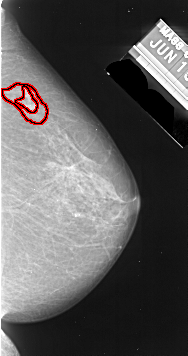

FILE: A_1007_1.RIGHT_MLO.OVERLAY

TOTAL_ABNORMALITIES 1

ABNORMALITY 1

LESION_TYPE MASS SHAPE IRREGULAR MARGINS SPICULATED

ASSESSMENT 5

SUBTLETY 4

PATHOLOGY MALIGNANT

TOTAL_OUTLINES 2

BOUNDARY

CORE